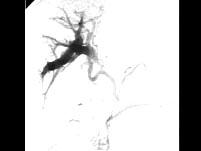

问题 微小肝癌主要通过哪项检查确定()

选项 A.AFP测定 B.B超检查 C.选择性肝动脉造影 D.放射性放射性核素肝扫描 E.MRI检查

答案 C